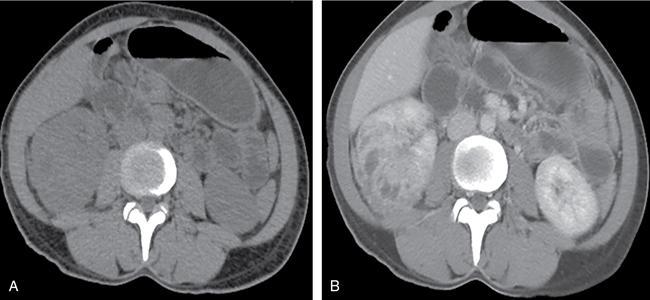

Renal fungal infections are rare, usually seen in immunocompromised patients and have increased mortality and morbidity. Many genitourinary fungal infections are confined to the bladder and urethra. Multiple imaging modalities aid in the primary diagnosis, follow-up and image-guided procedures. The most common causative pathogens are of the Candida species mainly Candida albicans, followed by Aspergillus spp., and Mucorales. Other fungi that have been described as causative pathogens include Rhizopus oryzae, Geotrichum candidu, Crypotoccci and Histoplasma. Pneumocystis jirovecii is implicated more commonly with retroviral disease. Renal fungal infections are rare, affect the neonates and elderly population. Common predisposing conditions include diabetes mellitus, urinary tract abnormalities, chronic indwelling catheters, immunocompromised state due to retroviral disease or postrenal transplant status, malignancy, prolonged antibiotic therapy, steroids and malnutrition. The pathogenesis of infection progresses through the phases of adherence, invasion of renal tissue, renal vascular invasion and subsequent dissemination. Complex infections can spread to the ureters and kidneys either through the haematogenous route or via ascending infection. Most patients are initially detected with candiduria, which develops into candidemia and disseminated candidiasis, thereby affecting the kidneys. Complex urinary infections are associated with fungal bezoars/balls/accretions results from aggregation of debris and necrotic tissue which are even rarer and may lead to obstructive uropathy. The fungal hyphae can aggressively invade the blood vessels, thereby leading to haemorrhage, thrombosis and infarction. This is most commonly seen in infections with Aspergillus and Mucor. Patients with renal fungal infection usually have systemic symptoms such as fever and can present as acute renal failure. Obstruction can cause diffuse abdominal pain or flank pain like a renal colic. With disseminated disease, features of sepsis set in. All patients with candiduria and underlying predisposing risk factors as mentioned before have to be carefully evaluated. Persistent candiduria in high-risk individuals should always prompt radiologic imaging of the kidneys and upper urinary tract with ultrasound or CT. On imaging, the commonly seen findings include initial renal microabscesses (parenchymal or subcapsular) which can progress to larger abscesses. Advanced disease leads to parenchymal necrosis and renal infarction. Fungal balls are also seen. Chronic and indolent infections may cause parenchymal calcifications. Though obsolete, conventional plain radiograph can demonstrate enlarged renal shadows with radiolucent fungal balls. On IVU, there may be nonvisualization of the affected kidney or delayed contrast excretion; and the fungal debris appears as filling defects within the opacified pelvicalyceal system. Secondary hydronephrosis due to obstruction by fungal ball may be seen. Unilateral renal involvement predominates over bilateral involvement. The affected kidney may appear bulky with indistinct corticomedullary differentiation. Presence of multiple small anechoic cystic foci with or without posterior acoustic enhancement areas represents microabscesses. Layered renal pelvic and calyceal wall thickening is seen with innermost hyperechoic rim representing the injured mucosal, central hypoechoic area represent submucosal oedema and infiltration and outermost thickest hyperechoic layer of muscularis. This layered arrangement of wall thickening is indefinitive sonological finding and is seen with other forms of pyelitis. On colour Doppler, peripelvic region and renal sinus may show increased vascularity. With progression of infection, the papilla is involved causing papillitis and resultant papillary necrosis, which serves as the nidus for fungal ball formation. Echogenic debris within a dilated pelvicalyceal system and ureter may be seen in early fungus ball formation. A fungal ball is seen as a mobile, echogenic, avascular mass with no posterior acoustic shadow in the renal pelvis, causing obstruction and hydronephrosis. Mobile intraluminal echogenic avascular mass with associated renal pelvic wall thickening favours an ongoing inflammatory process as opposed to a neoplasm. Associated renal arterial or venous thrombosis may be seen especially in invasive fungal infections. Interval follow-up with ultrasound should be done to look for the dissolution of the fungal ball, renal size, parenchymal echogenicity and grade of obstruction of the pelvicalyceal system. Globular enlargement of kidneys with reduced perfusion is visualized as poor heterogeneous contrast enhancement (salt and pepper appearance). Microabscesses are seen as small hypoattenuating parenchymal or subcapsular lesions (Fig. 10.12.2.8.1). Fungal balls are seen as rounded, heterogeneous soft-tissue attenuation lesions with variable contrast enhancement. They do not show any attachment to the walls of the urinary tract and are seen as filling defects on the excretory phase of CT urogram.